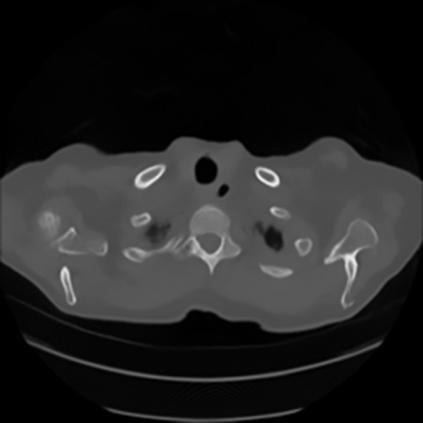

Sparse-view computed tomography (CT) -- using a small number of projections for tomographic reconstruction -- enables much lower radiation dose to patients and accelerated data acquisition. The reconstructed images, however, suffer from strong artifacts, greatly limiting their diagnostic value. Current trends for sparse-view CT turn to the raw data for better information recovery. The resultant dual-domain methods, nonetheless, suffer from secondary artifacts, especially in ultra-sparse view scenarios, and their generalization to other scanners/protocols is greatly limited. A crucial question arises: have the image post-processing methods reached the limit? Our answer is not yet. In this paper, we stick to image post-processing methods due to great flexibility and propose global representation (GloRe) distillation framework for sparse-view CT, termed GloReDi. First, we propose to learn GloRe with Fourier convolution, so each element in GloRe has an image-wide receptive field. Second, unlike methods that only use the full-view images for supervision, we propose to distill GloRe from intermediate-view reconstructed images that are readily available but not explored in previous literature. The success of GloRe distillation is attributed to two key components: representation directional distillation to align the GloRe directions, and band-pass-specific contrastive distillation to gain clinically important details. Extensive experiments demonstrate the superiority of the proposed GloReDi over the state-of-the-art methods, including dual-domain ones. The source code is available at https://github.com/longzilicart/GloReDi.